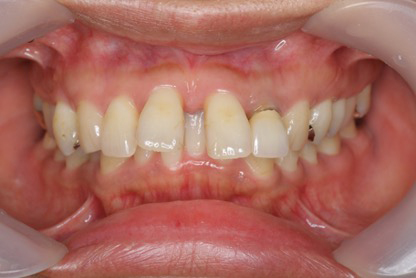

本来あるべき歯並びに矯正することで機能的なかみ合わせを実現させる歯科矯正を行うことで全身の健康にもつながります。審美性に目が向けられがちですが、当院では「かみ合わせ」を整えることで本当の美しさを目指しています。

ほとんどの症例で小臼歯の抜歯せずに治療できる「ゴムメタル」という金属のワイヤーを使用した歯科矯正とマウスピース「インビザライン・システム」を使ったインビザライン矯正があります。インビザライン矯正は日中でも必要に応じて取り外しができ、食事の制限がなく、治療中も好きな食べ物を我慢する必要がありません。また、いつでも簡単に歯のお手入れができ、口腔内を健康に保つことができます。

治療前に顎機能検査(CADIAX)で顎の動きを検査し、一人ひとりに合わせた綿密な治療計画を策定してから治療を行います。咬み合わせの状況や骨格など、難易度によりますが、ワイヤー矯正では2〜3年、マウスピース矯正で2~4年程度の期間をかけて歯を正しい位置へ移動させます。